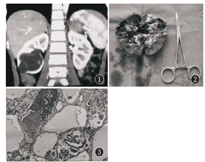

患儿,男,7岁9个月,因腹痛伴呕吐体检发现右肾囊肿伴结石2个月收入院。患儿入院时已无腹痛及呕吐等症状。查体:腹部平软,未触及包块,双侧肾区无叩击痛,心肺无异常。化验检查血常规:WBC 5.34×109/L,RBC 4.72×1012/L,血红蛋白135.0 g/L,红细胞比容44%,血小板278×109/L;生化:丙氨酸氨基转移酶23 U/L,天冬氨酸氨基转移酶28 U/L,尿素4.91 mmol/L,肌酐63 μmol/L,电解质及尿常规均正常。2个月前的多层螺旋CT尿路造影提示:右肾中下极多发低密度灶,范围约5.1 cm×4.0 cm,其内可见高密度影,边界欠清,腹膜后未见明显肿大淋巴结,左肾正常,考虑多发性肾囊肿可能,右肾结石(图1)。本次入院复查彩超提示:右肾囊性病灶,右肾多发结石伴右肾轻度积水,左肾正常;胸片未见异常,腹部平片未见阳性结石征象。术前诊断:右肾囊性病变:肾囊肿?囊性肾瘤?囊性肾母细胞瘤?治疗行右肾切除及肿瘤切除术,术中见右肾绝大部分被瘤体占据,仅上极有部分正常肾组织存留,集合系统受侵犯,瘤体包膜完整,质地较硬,剖面呈多房性,囊液清黄色,囊肿壁呈白色纤维状,无正常肾实质结构,瘤体中心可见少许坏死灶,未见结石(图2)。病理报告:CPDN(输尿管断端未见肿瘤组织)。免疫组织化学:波形蛋白、Wilms肿瘤蛋白-1、胶质纤维酸性蛋白、上皮膜抗原均为(+),结蛋白灶性(+),神经元特异性烯醇化酶、酸性钙结合蛋白S-100(-),蛋白Ki-67标记指数约60%(图3)。术后患儿恢复良好,未进行放化疗,8个月随访,无复发及转移。